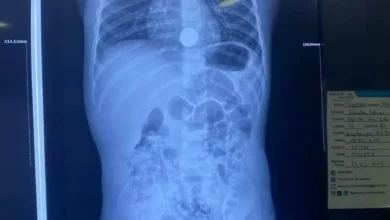

Niña tragó moneda de 10 centavos y terminó en el hospital

La niña Luana tragó moneda de 10 centavos en Riobamba y puso en apuros a sus padres y abuelos que…